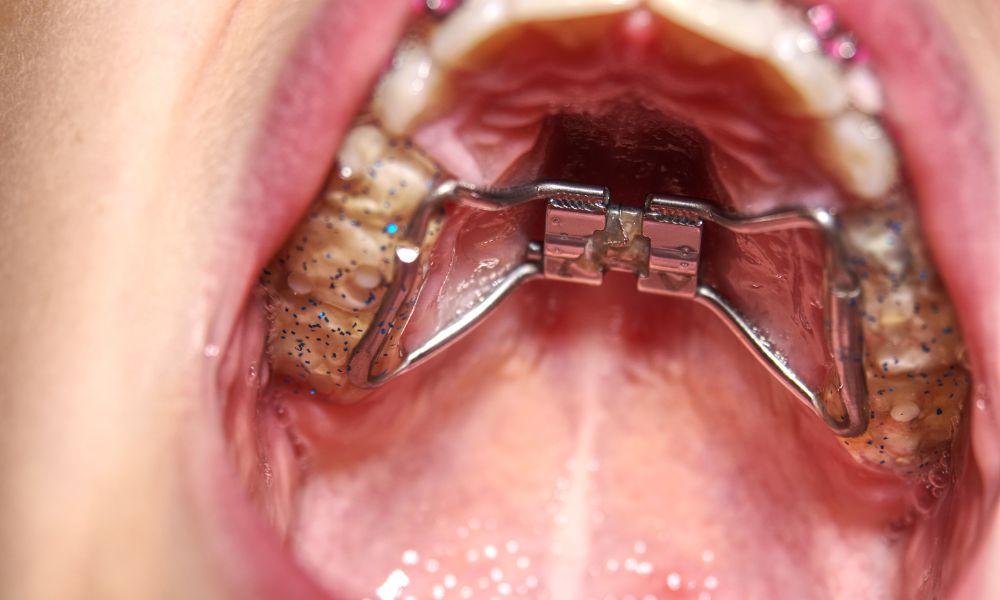

Expansores palatinos: una solución eficaz para casos leves a moderados

Los expansores palatinos son ideales para niños y adolescentes con paladar estrecho. Estos aparatos aplican presión suave al maxilar superior, estimulando su ensanchamiento. Estudios muestran que mejoran la oclusión dental y evitan problemas como el apiñamiento.

En la Clínica Birbe, tenemos más de 20 años tratando el paladar estrecho. Nuestros ortodoncistas diagnostican minuciosamente para elegir el expansor adecuado. Así, aseguramos resultados óptimos y duraderos para cada paciente.

En casos complejos, la cirugía puede ser necesaria. La SARPE o MARPE son técnicas para expandir el paladar en adultos. Estas cirugías mejoran la función oral y la estética facial de manera efectiva.